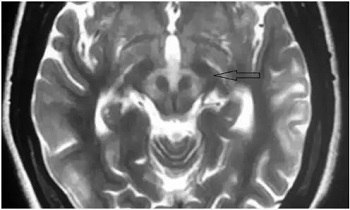

在查房的间隙,贾映海教授便在走廊里继续开讲起“走廊课堂”——“何谓熊猫征”来。贾映海教授说,“熊猫征”主要有“大熊猫脸征”和“小熊猫脸征”。其中,“大熊猫脸征”,红核在T2WI上呈现对称性的低信号,为大熊猫的眼,红核周围的内侧丘系、大脑脚上部、红核脊髓束及皮质脑干束神经纤维受累表现为T2高信号, 构成大熊猫脸上半部白色的轮廓;而双侧上丘、中脑导水管周围灰质神经核团正常的短T2信号及中脑导水管的长T2信号构成了大熊猫脸的下半部。